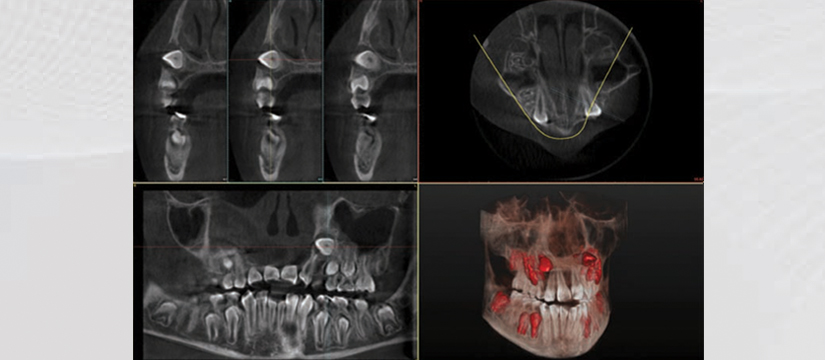

Klinika jonë premton se do t’ju ofrojë gjithnjë cilësinë më të lartë të shërbimit, me fjalën më të fundit të teknologjisë. Së fundmi ne jemi pajisur me pajisjen OWANDY IMAX TOUCH 3D. Kjo pajisje siguron me thjeshtësi dhe efikasitet imazhe high-definition për një diagnostikim të pagabueshëm. OWANDY është lideri i prodhimit të pajisjeve radiografike dentare në Francë, Amerikë, Gjermani e më gjerë. Produkti më i ri i OWANDY I-Max Touch 3D siguron të gjitha shërbimet radiografike në një aparaturë të vetme.

Aparatura posedon 17 programe të ndryshme ku mund të behën incizime si:

- Egzaminim i Sinusit

- 3D Pozicioni i sinusit